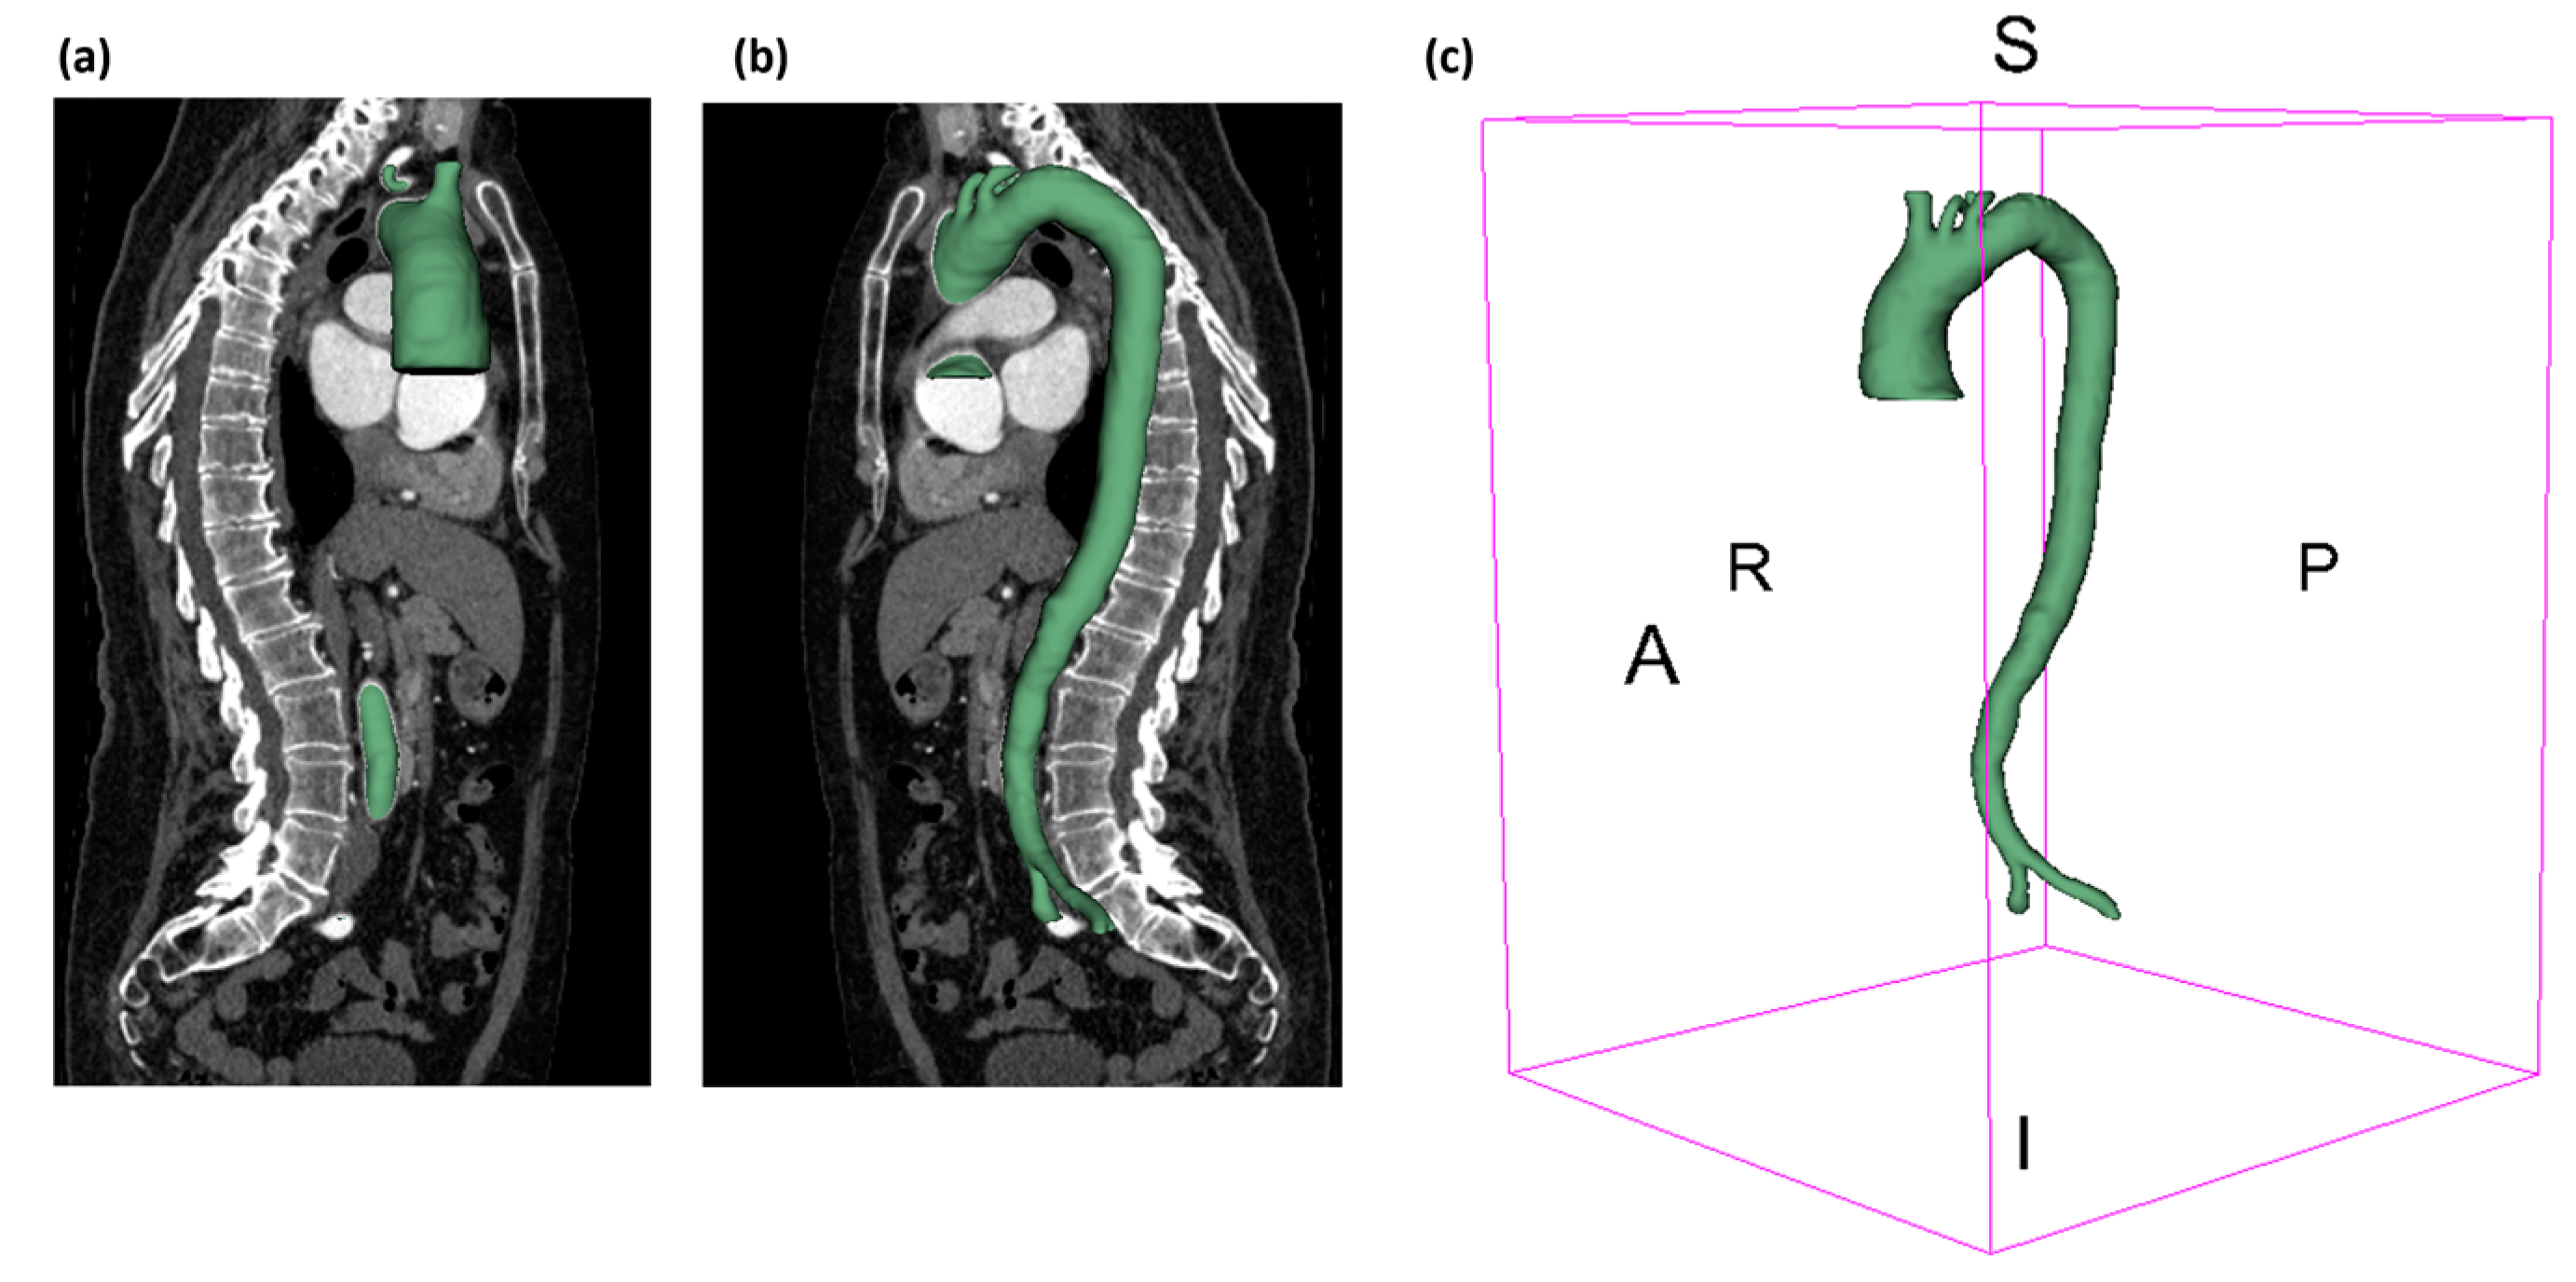

2.2. 3D Geometry